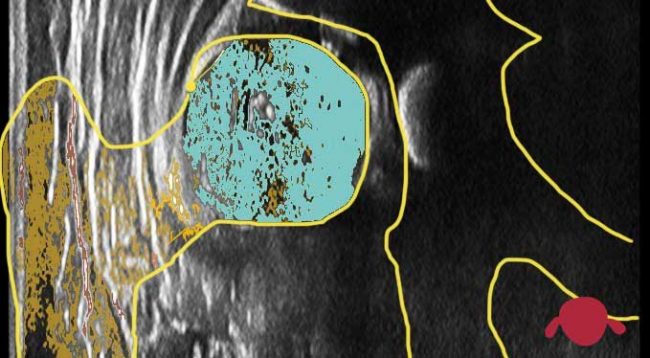

Un yeso pelvipédico o espica de yeso es una escayola que va desde el ombligo hasta los pies. Hay ciertas variaciones: pie incluído, tobillero o “pantalón corto”. Muchos tiene barra entre las piernas, se puede usar para sujetar al niño. Pero todos te complican la vida en cuatro puntos: 1) cambiar el pañal…